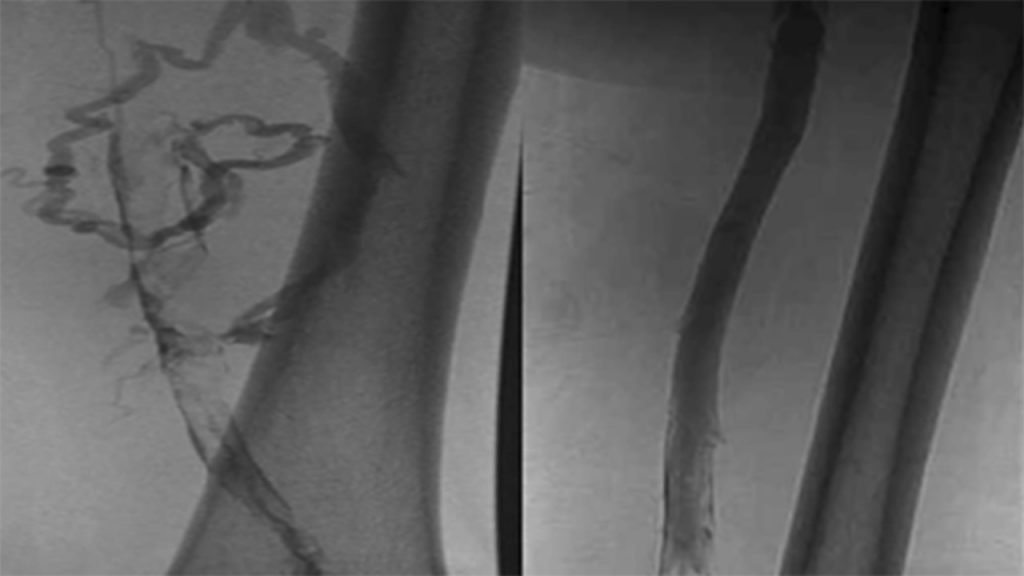

Diagnostic Procedures Some patients may experience DVT just once, but for others, the condition may become chronic. Since DVTs can be life threatening, getting a proper diagnosis is crucial. A doctor may use a combination of a physical exam, medical history and one of several tools to make a diagnosis.1 Photos of Diagnostic Procedures

Despite serious complications, DVT can be treated if detected early. Certain treatments may work for some patients, but not others. A vascular specialist may recommend treatments that prevent the blood clot from enlarging and moving to the lungs or other therapies to dissolve the clot right away. These treatments may include:3 Photos of DVT Treatments